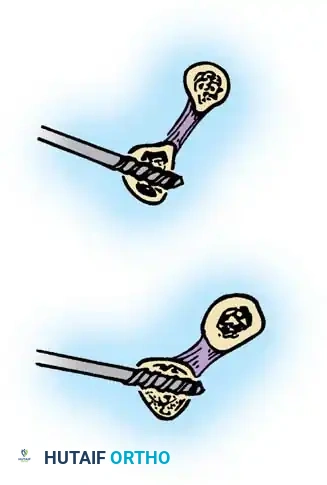

Intraarticular Cruciate Ligament Reconstruction

Arafiles described the creation of an intraarticular "cruciate" ligament using tendon grafts to stabilize the joint while allowing flexion-extension exercises as early as 6 days postoperatively.

Fig. 58-24 A and B, Slot in trochlea and drill holes showing the course of the tendon graft. C and D, Completed repair acting as an intraarticular cruciate ligament. (From Arafiles RP: Neglected posterior dislocation of the elbow, J Bone Joint Surg 69B:199, 1987.)